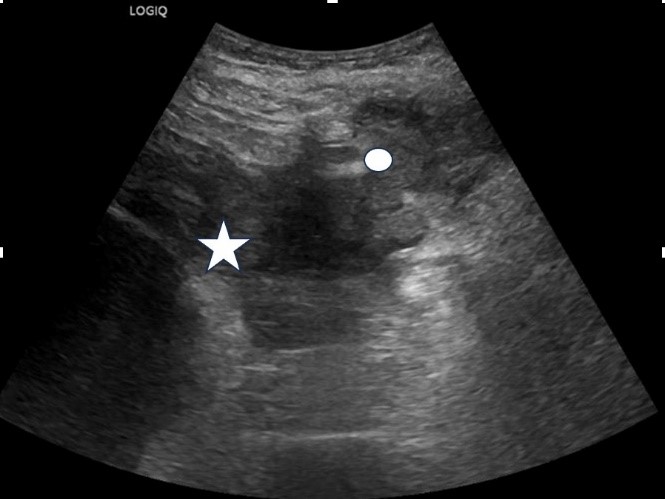

B-mode ultrasound demonstrated gross left sided hydronephrosis with thinning of the renal cortex which is in keeping with previous imaging (fig1). However, deep to the clinically obvious swelling on the left flank there was an irregular heterogeneous fluid collection which extended from the superficial soft tissues/skin to the lower pole region of the left kidney with which it appeared intimately associated (fig2, fig3 and Fig 4). These findings were concerning for a large renal abscess which may have progressed to a perirenal abscess and developed a sinus tract extending to the skin surface. In light of the elevated CRP, urgent cross-sectional imaging and urgent clinical review by the urology team was conducted. The right kidney and urinary bladder were unremarkable on ultrasound.

| Figure 1: Left sided hydronephrosis with renal cortical thinning (Star: Dilated collecting system, Triangle: Thinned cortex) |